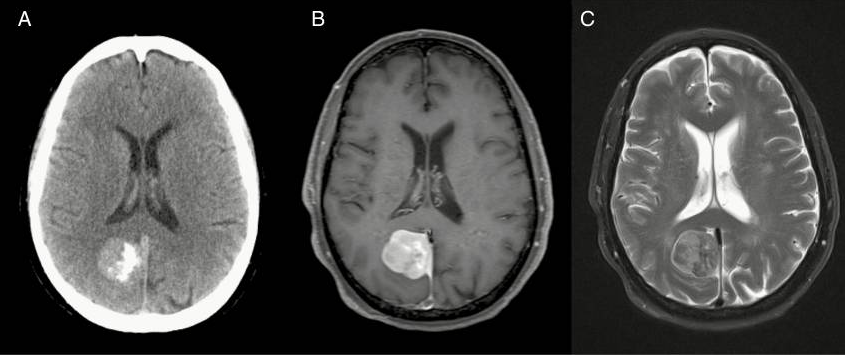

戈弗雷·豪恩菲尔德爵士在1973年引入了计算机断层扫描,保罗·劳特布尔在1973年引入了磁共振成像,这开启了影像学在脑膜瘤诊断和治疗中的重要作用。这些强有力的方法,加上静脉注射造影剂,阐明了脑膜瘤的轴外解剖起源,它们的生长模式,硬脑膜的扩散经常远远超出肿瘤体积的限制,邻近骨的可变受累,溶解或骨质增生的变化,以及神经血管结构的典型受累和偏斜。通过CT和MRI对脑膜瘤外观和邻近组织的独特分辨率刺激了术前计划和手术技术的平行发展,增强了对手术风险的认识,并允许从多个间隔区更明确地切除脑膜瘤。此外,重要的动脉和静脉关系现在可以用计算机断层扫描或磁共振血管造影术进行更详细的研究。

脑膜瘤的影像学诊断通常依赖于计算机断层扫描和核磁共振成像的评估。然而,将残留或复发的肿瘤与手术后或放射治疗的变化区分开来有时可能具有挑战性。在这些情况下,现代成像技术已经利用了脑膜瘤生物学的特定属性:例如,核闪烁扫描或正电子发射断层扫描(正电子发射断层扫描)可以检测放射性标记的奥曲肽(一种生长抑素激动剂)及其与肿瘤特异性生长抑素受体的结合(如SSTRⅱ)。

常规的计算机断层扫描和现在的核磁共振成像提供了一种可靠的非侵入性方法来跟踪肿瘤的生长,允许在无症状患者随后进行成像的情况下推导脑膜瘤的自然病史。虽然在神经外科的早期,影像学用于在患者出现神经症状后验证和定位肿瘤,但现在肿瘤经常被偶然发现。决定用连续成像来治疗或跟踪假定的脑膜瘤,激发了人们仅从成像特征来评估肿瘤行为甚至分级的兴趣。这就要求对那些在较初确诊时肿瘤较小且无症状的患者需要治疗进行严格评估。这导致了对传统磁共振成像以及前沿成像模式(如磁共振波谱或正电子发射断层扫描)上特定特征的详细检查,以便从成像特征推断肿瘤行为。